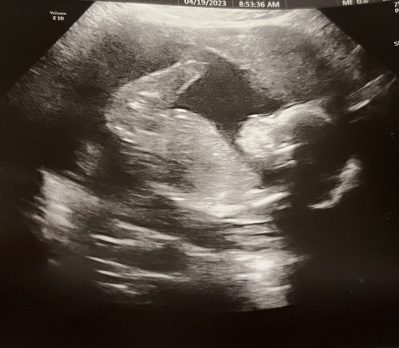

Before I got on the train to NYC, I got to see my 20 week old granddaughter (in the uterus, that is).

Your granddaughter is beautiful. Sending love.